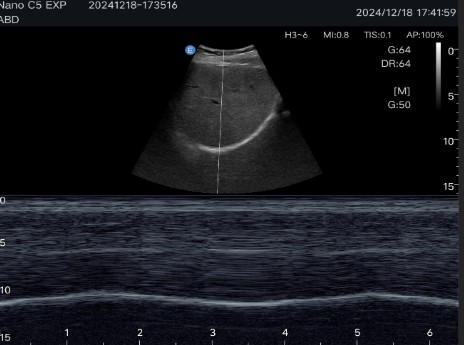

Abdominal diagnostics, obstetrics and gynecology: Allows detailed evaluation of internal organs and structures.

Multiple imaging modes: Includes B-mode, C-mode, M-mode and Pulsed Doppler (PW), ensuring precise visualizations for various clinical applications.